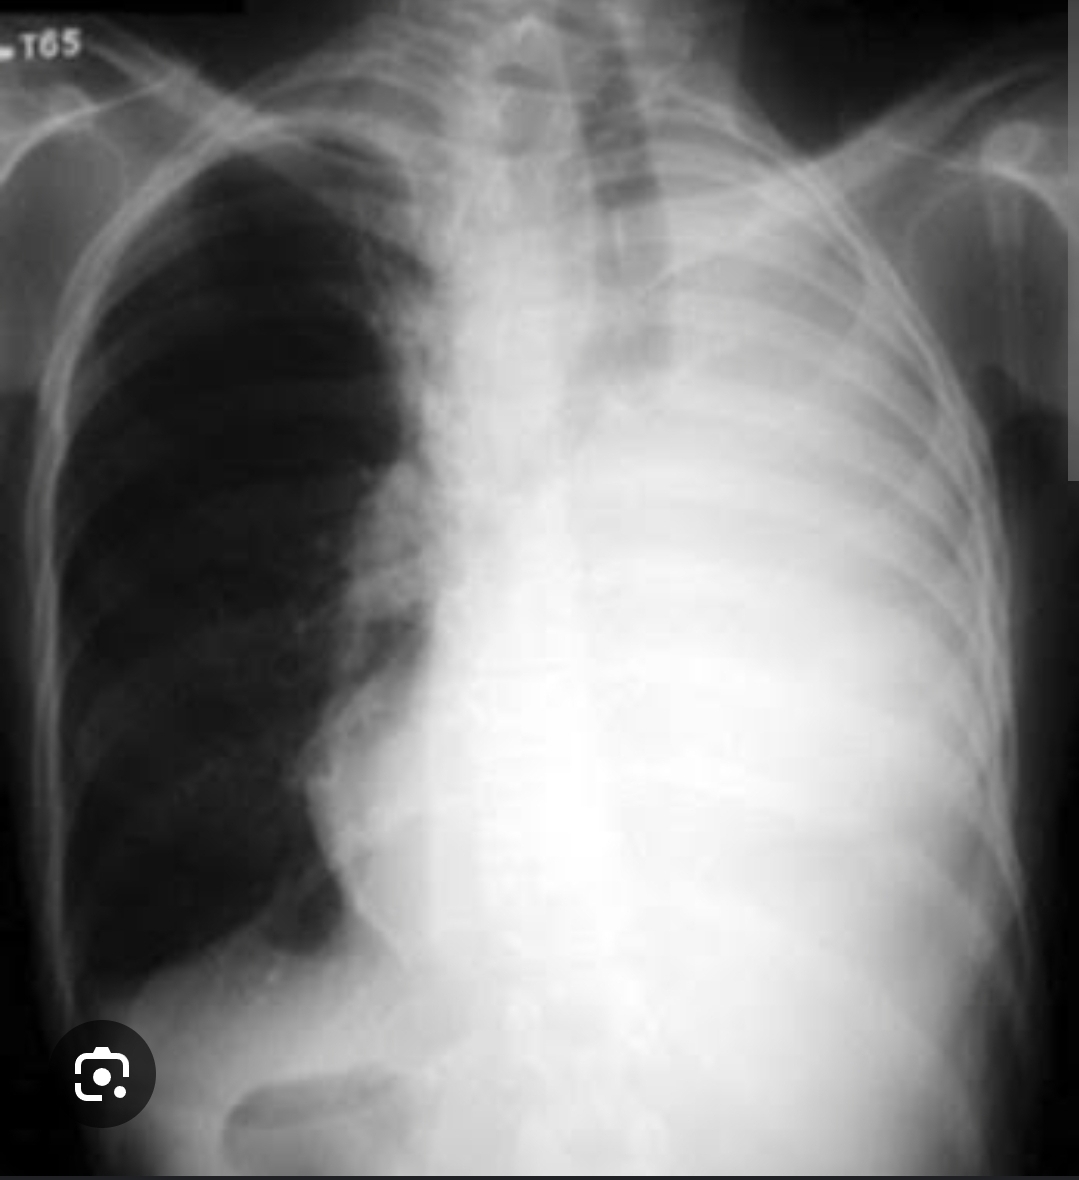

Como se dá o padrão de consolidação?

Broncograma aéreo ( contorno dos brônquios) + radiopacidade mal delimitado + volume preservado

Q

Radiopacidade homogêneo + diminuição do volume + retração de estruturas adjacente pra perto